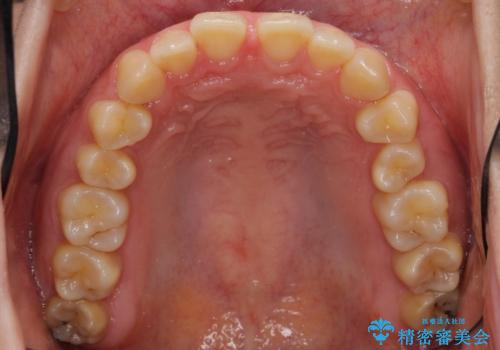

前歯のすきま 右上の小臼歯の垂直的骨吸収を抜歯で解決

- 前歯のすきまを気にして来院。

奥歯が1歯対1歯で、過蓋咬合を呈していました。

レントゲンで、右上4番の近心の垂直的骨欠損があり、抜歯を行うこととしました。